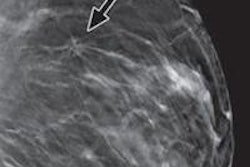

Several recent studies have reported the benefits of combined tomosynthesis and mammography over conventional digital mammography alone, including improved performance and diagnostic accuracy, reduced recall rates, and higher cancer detection rates. In light of these benefits, many centers are combining tomosynthesis and mammography for screening and diagnostic applications.

For the study, Dang and colleagues invited 10 radiologists to read images from cases in which screening digital mammography was used alone or screening mammography was combined with tomosynthesis. The radiologists read images from 3,665 examinations (1,502 tomosynthesis and mammography cases and 2,163 digital mammography studies) from July 2012 to January 2013. Dang's team recorded the number of cases reported per hour, per radiologist.

The mean number of studies interpreted per hour was 24 for combined tomosynthesis and mammography, compared with 34 for digital mammography alone. A mean of 10 fewer studies were interpreted per hour for combined tomosynthesis and mammography, the researchers found.

Mean interpretation time was 2.8 minutes for combined tomosynthesis and mammography and 1.9 minutes for digital mammography, according to the authors. Interpretation time with tomosynthesis and mammography was 47% longer than with digital mammography alone.